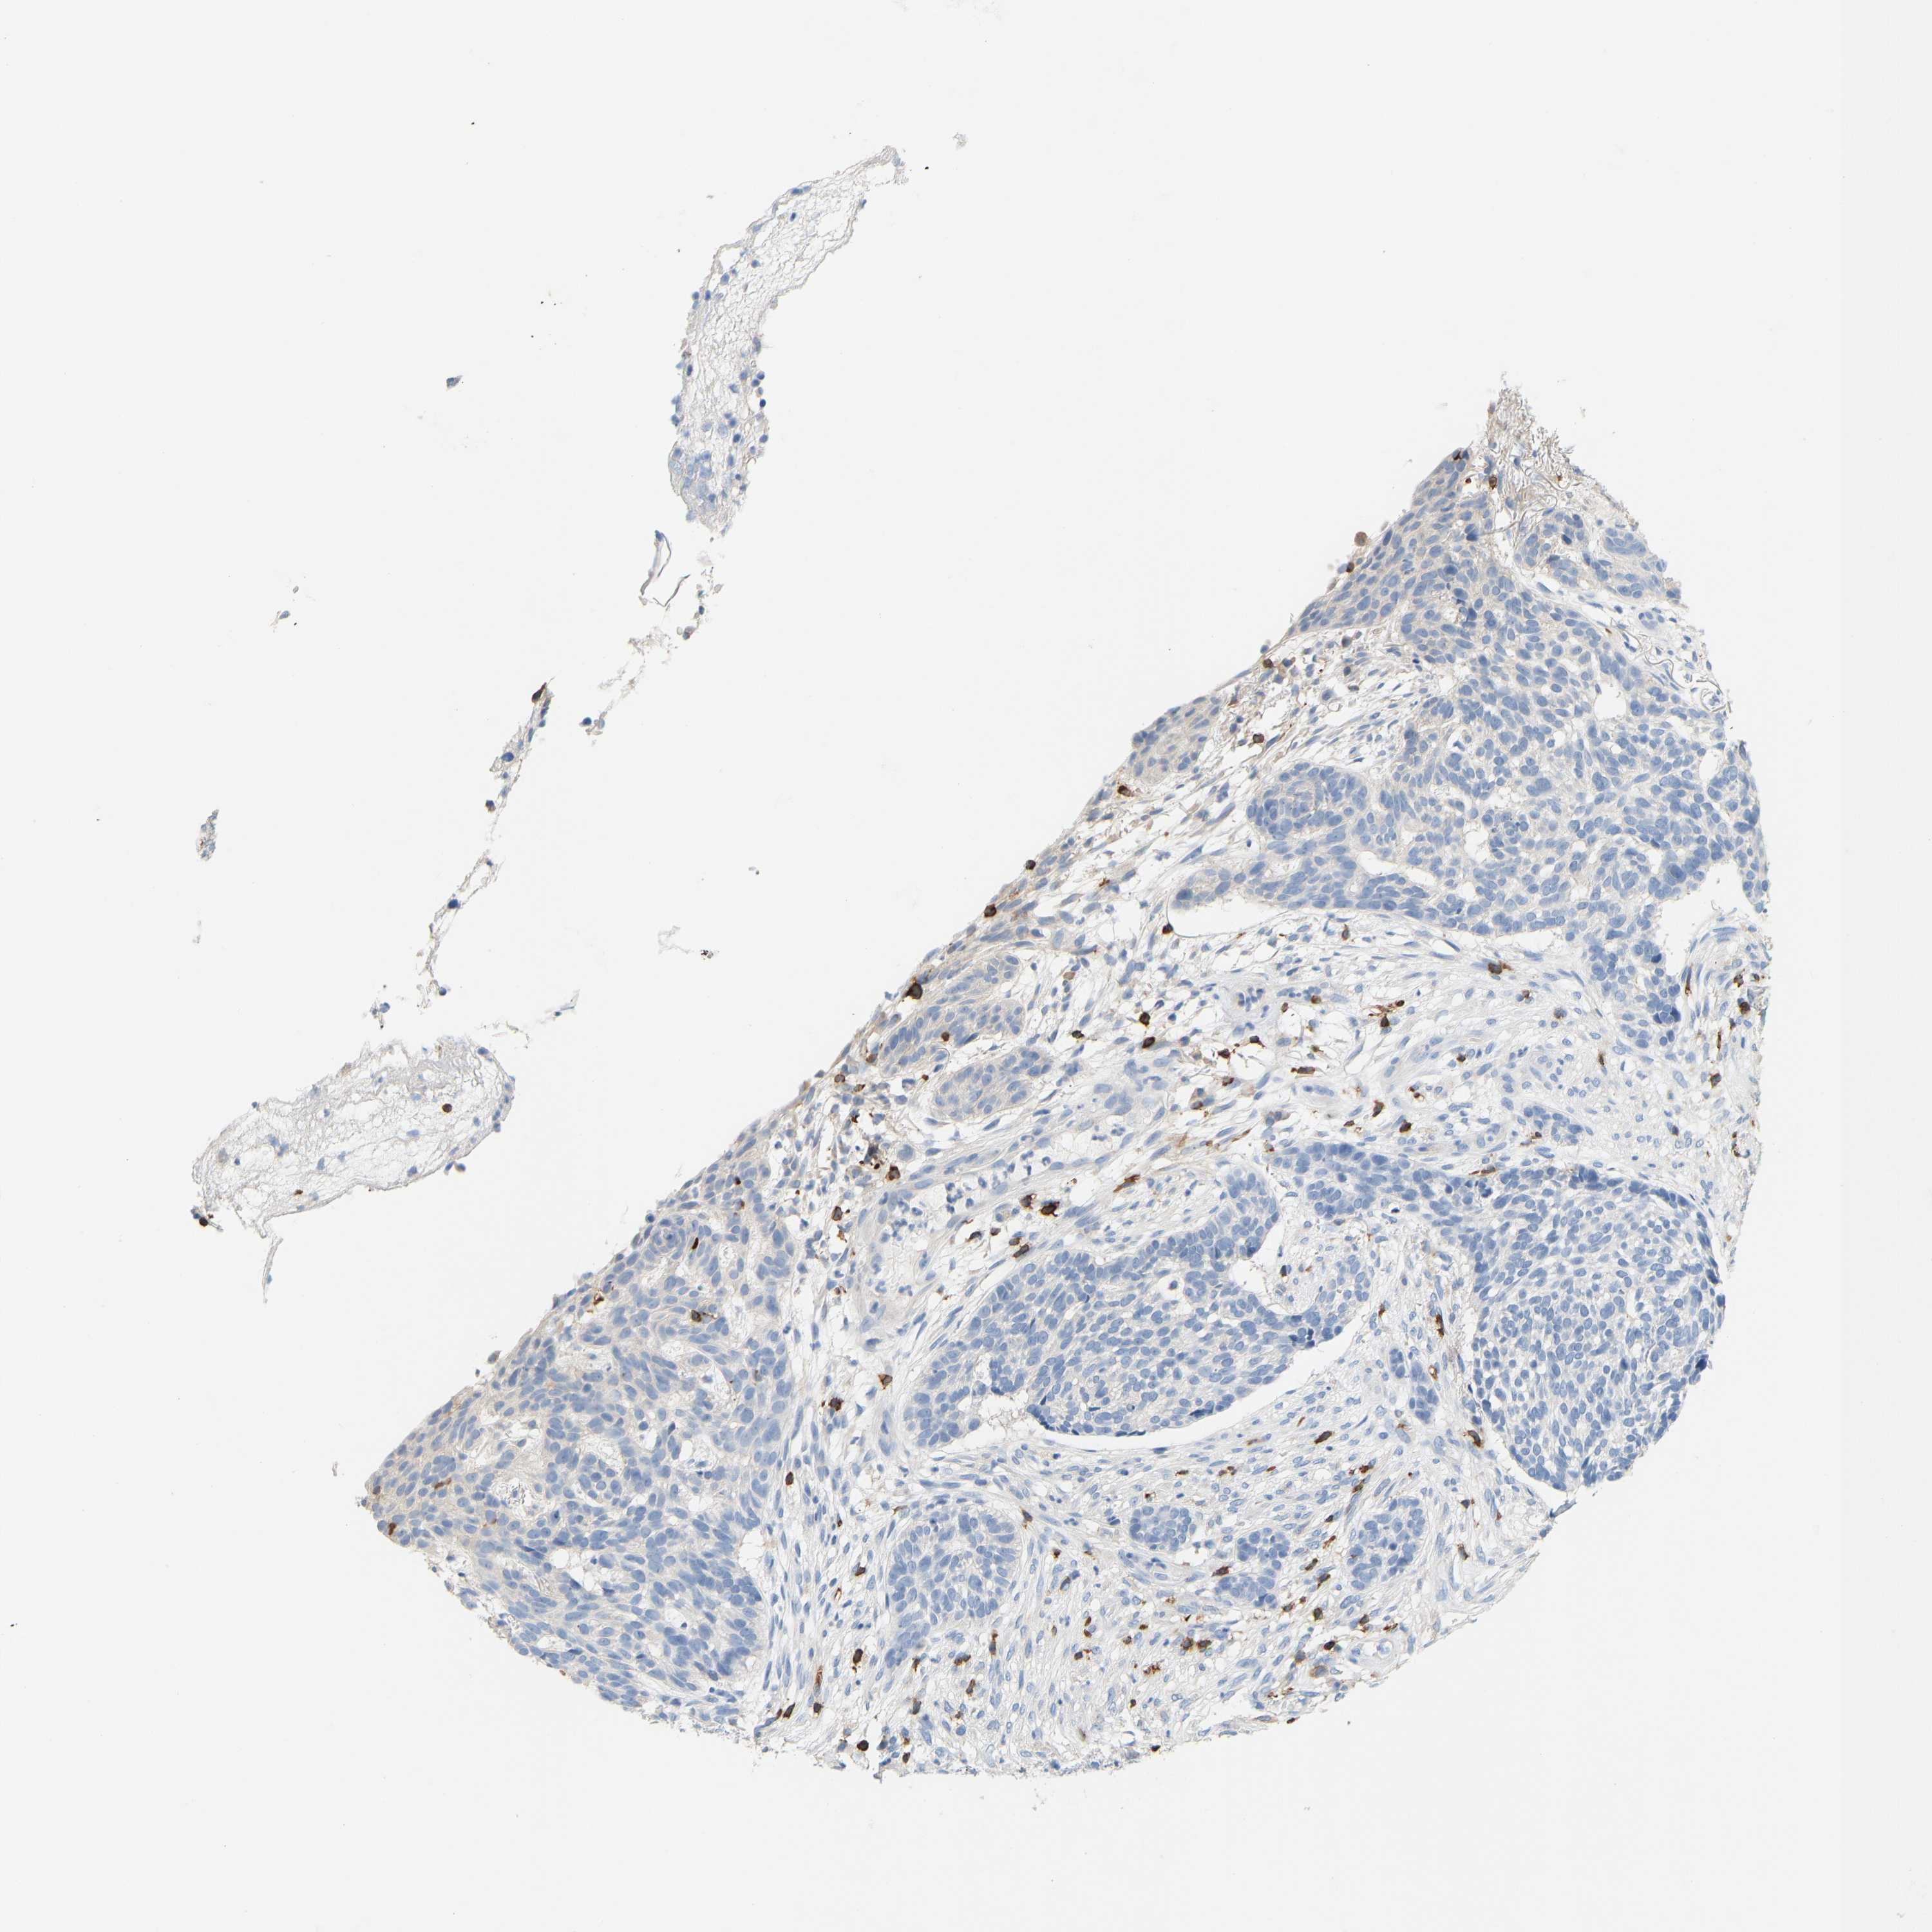

SKIN CANCER - Protein expressioni

A mouse-over function shows sample information and annotation data. Click on an image to view it in a full screen mode. Samples can be filtered based on level of antibody staining by selecting one or several of the following categories: high, medium, low and not detected. The assay and annotation is described here.

Antibody stainingi

Antibody staining in the annotated cell types in the current human tissue is reported as not detected, low, medium, or high, based on conventional immunohistochemistry profiling in selected tissues. This score is based on the combination of the staining intensity and fraction of stained cells.

Each image is clickable and will lead to virtual microscopy that enables deeper exploration of all samples and also displays staining intensity scores, fraction scores and subcellular localization as well as patient and tissue information for each sample.

Antibody HPA018849

Antibody HPA019536

Antibody CAB033987

Basal cell carcinoma

Squamous cell carcinoma, NOS

Squamous cell carcinoma, metastatic, NOS